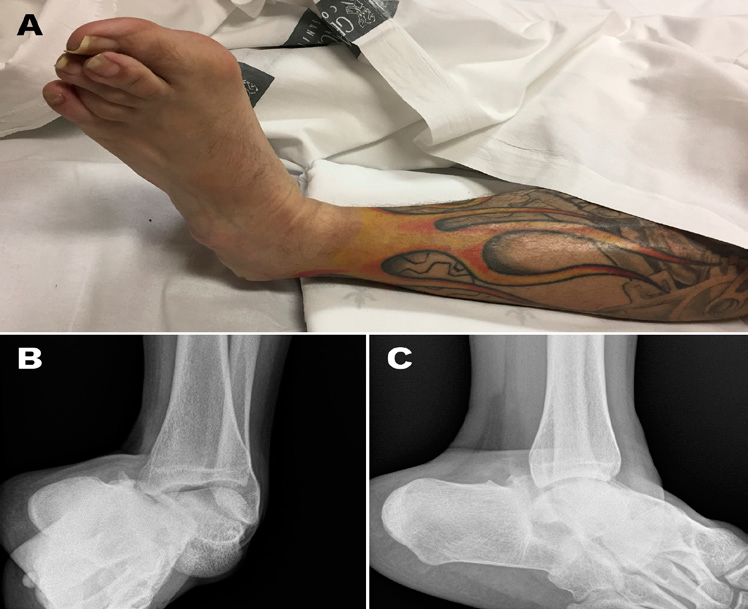

We report the case of a 32-year-old Caucasian male patient who was brought to the Emergency Room of our hospital after suffering a fall with ankle inversion mechanism while practicing sports with a BMX-type bicycle. Physical examination revealed intense pain located in the left ankle, swelling and deformity of the hindfoot with medial plantar flexion, prominence of bony structures in the lateral region of the joint, abrasions and ecchymosis without deep wounds (Figure 1A). The patient was hemodynamically stable and did not associate other lesions. The neurovascular status of the limb was evaluated by checking the presence of the dorsalis pedis and posterior tibial pulse, correct nail capillary refill and preservation of sensitivity by two-point discrimination test.

Conventional X-ray revealed a peritalar dislocation with displacement of the calcaneus and rest of the bones of the foot towards the medial side without observing associated fractures (Figure 1B & 1C).

Figure 1A ankle appearance on arrival to the Emergency Room; B: conventional X-Ray (B, anteroposterior view; C, lateral view) showing pure peritalar dislocation.